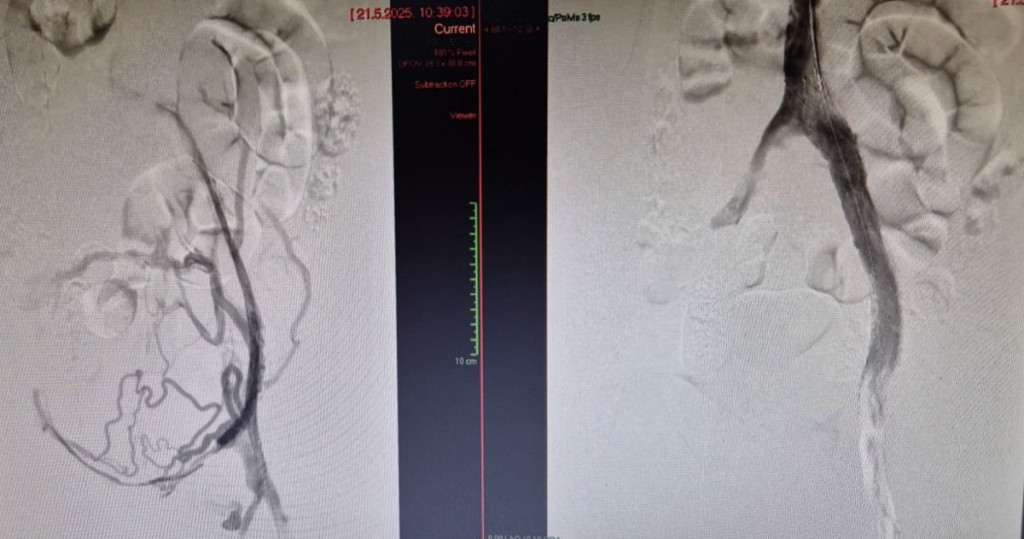

Na Odeljenju za interventnu radiologiju Univerzitetskog kliničkog centra Vojvodine (UKCV) uspešno je izvedena prva endovaskularna intervencija na bedrenim venama u Srbiji.

Ova inovativna procedura sprovedena je kod pacijentkinje (24) sa okluzijom bedrenih vena, izazvanom hroničnom trombozom dubokih vena. Tokom intervencije, plasiran je specijalni venski stent.

Zahvat su izveli interventni radiolozi dr Slobodan Torbica i dr Andrej Petreš, uz stručno proktorstvo prof. dr Suata Doğancija iz Turske, jednog od vodećih evropskih stručnjaka u oblasti venske patologije.

"Uvođenje ove procedure u kliničku praksu UKCV-a predstavlja značajan iskorak u tretmanu hroničnih venskih oboljenja, jer po prvi put pacijentima u Srbiji omogućava primenu savremenog, minimalno invazivnog terapijskog pristupa koji je do sada bio nedostupan u domaćem zdravstvenom sistemu", kažu u KC Vojvodina.